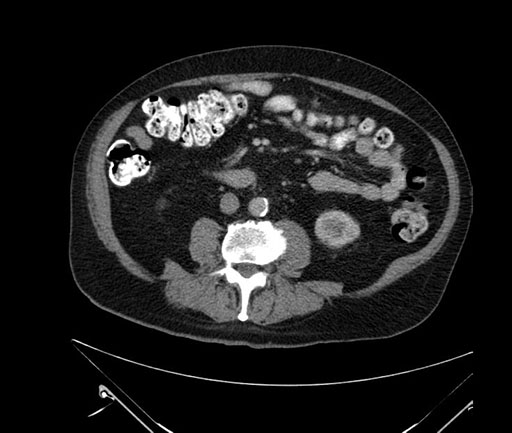

Imaging Analysis

Look through the patient's CT scan to identify any areas of concern for the necessary procedure.

Based on your CT findings, which issue(s) would give reason for "planned slowing down moment(s)" in this case?

Considering a standard Whipple procedure, what step(s) of the operation would you do differently in this case?